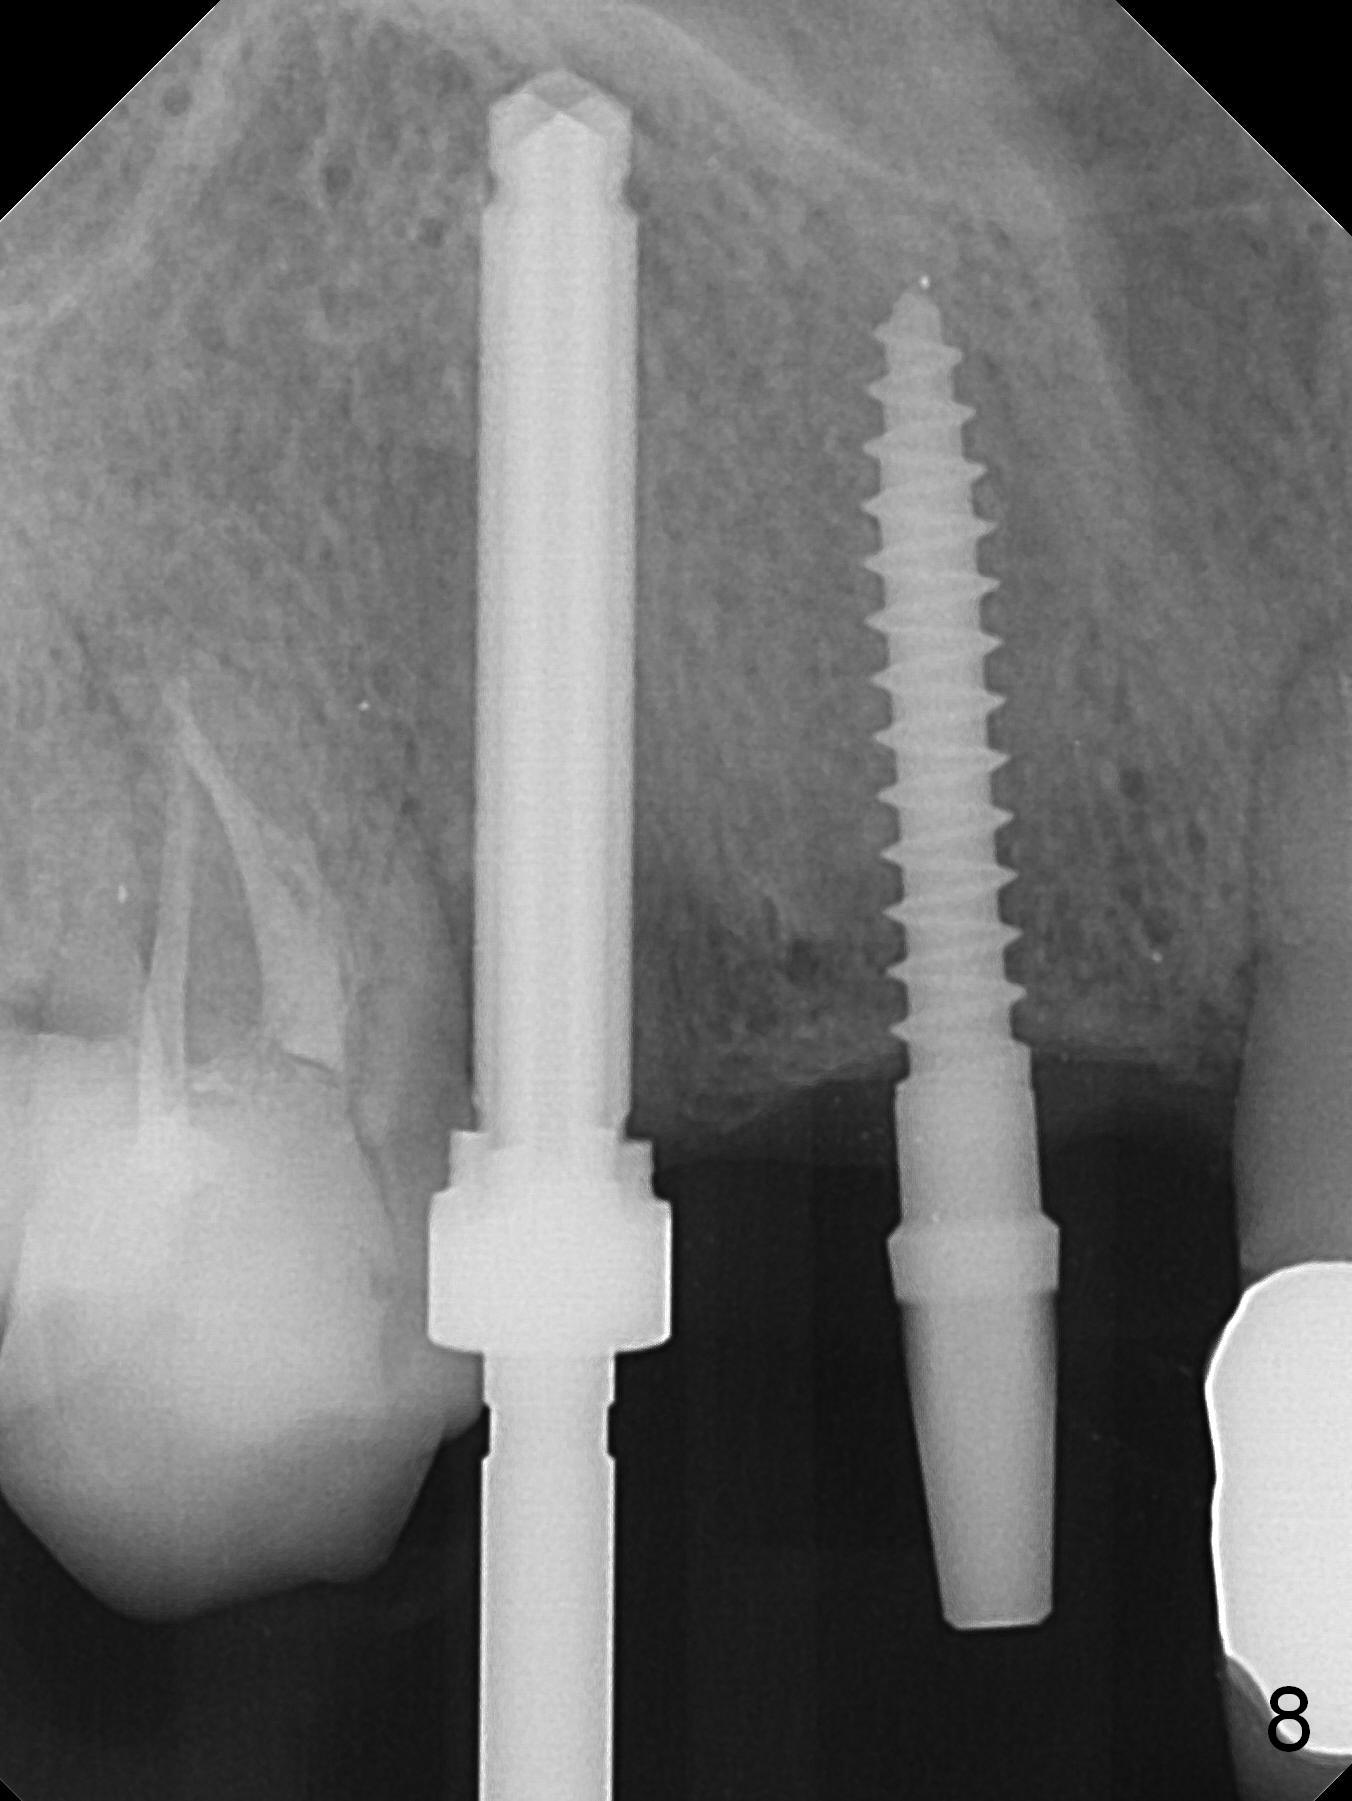

When the bridge is sectioned between #7 and 8, the tooth #6 is found non-salvageable (Fig.1). Incision shows the atrophic buccal plate at #7 (Fig.2 arrowheads); to prevent the same feature from happening at #6 with thin buccal plate, the most buccal portion of the root is preserved (socket shield (Fig.2-4: *)). The initial osteotomy is established in the palatal slope at #6 (Fig.5 circle) with 1.5 mm drill (Fig.6,7). A portion of the root is visible in Fig.6 (arrowheads). After sequential osteotomy with 2 mm, 3 mm (Fig.8) and 3.2 mm drills, a 4x15 mm implant is placed (Fig.10). To accommodate the cross bite, the coronal portion of the implant (Fig.9 white circle) is positioned close to the socket shield. It appears that the shield prevents the implant from encroaching the buccal plate.

Since the ridge at #7 is ~ 4 mm, a 2.5x14 mm 1-piece implant is placed (Fig.8) after 1.2 mm (Fig.7), and 1.5 mm drills at 12 mm and 2 mm drill at 8 mm. Later the implant is placed deeper (Fig.10). There is no bone loss 7 or 12 months postop, respectively (Fig.11,12). After Diode gingivectomy, there is papillary formation (Fig.13). No provisional is provided after impression (with the abutment torqued at #6) for oral hygiene. With access holes at #6 and 7, crowns are bonded with minimal residual cement (Fig.14 <, which is removed later). There is no hard (Fig.15,16) or soft (Fig.17 *) atrophy 26 months postop, i.e., 13 months post cementation, due to the presence of socket shield (Fig.15 <, as compared to Fig.1). In fact the tooth #8 has mobility and fremitus (short root/poor crown/root ratio, Fig.16); occlusal adjustment is done 13 months post cementation. The crown is dislodged 2 years 1 month post cementation; a prefabricated post is being tried in (Fig.18). There is no atrophy, bone loss or infection at #6 (with socket sheath (*)) or 7 two years 5 months post cementation (Fig.20-27).